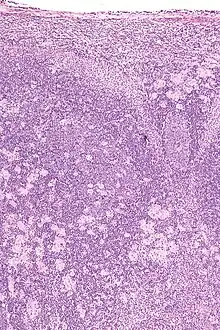

Cerebral toxoplasmosis (with primary involvement in the right occipital lobe)

Cerebral toxoplasmosis

High magnification micrograph of toxoplasmosis

Brain biopsy-High magnification micrograph of toxoplasmosis

Immunohistochemistry displaying positive Toxoplasma gondii trophozoites in a brain biopsy of a HIV immunocompromised individual

Real-time PCR is useful in pathogen detection, gene expression and regulation, and allelic discrimination. This PCR technique utilizes the 5' nuclease activity of Taq DNA polymerase to cleave a nonextendible, fluorescence-labeled hybridization probe during the extension phase of PCR.[63] A second fluorescent dye, e.g., 6-carboxy-tetramethyl-rhodamine, quenches the fluorescence of the intact probe.[63] The nuclease cleavage of the hybridization probe during the PCR releases the effect of quenching resulting in an increase of fluorescence proportional to the amount of PCR product, which can be monitored by a sequence detector.[63] Lymph nodes affected by Toxoplasma have characteristic changes, including poorly demarcated reactive germinal centers, and scattered epithelioid histiocytes.[64]